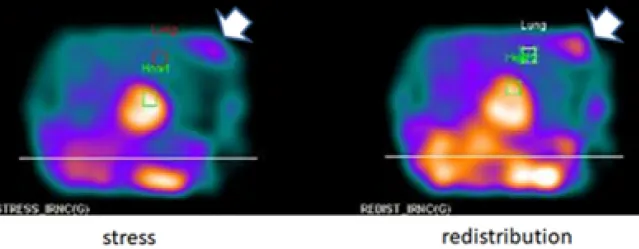

【115-1 醫學(三) 第14題】有關核醫心肌灌注掃描,下列敘述何者最不適當?